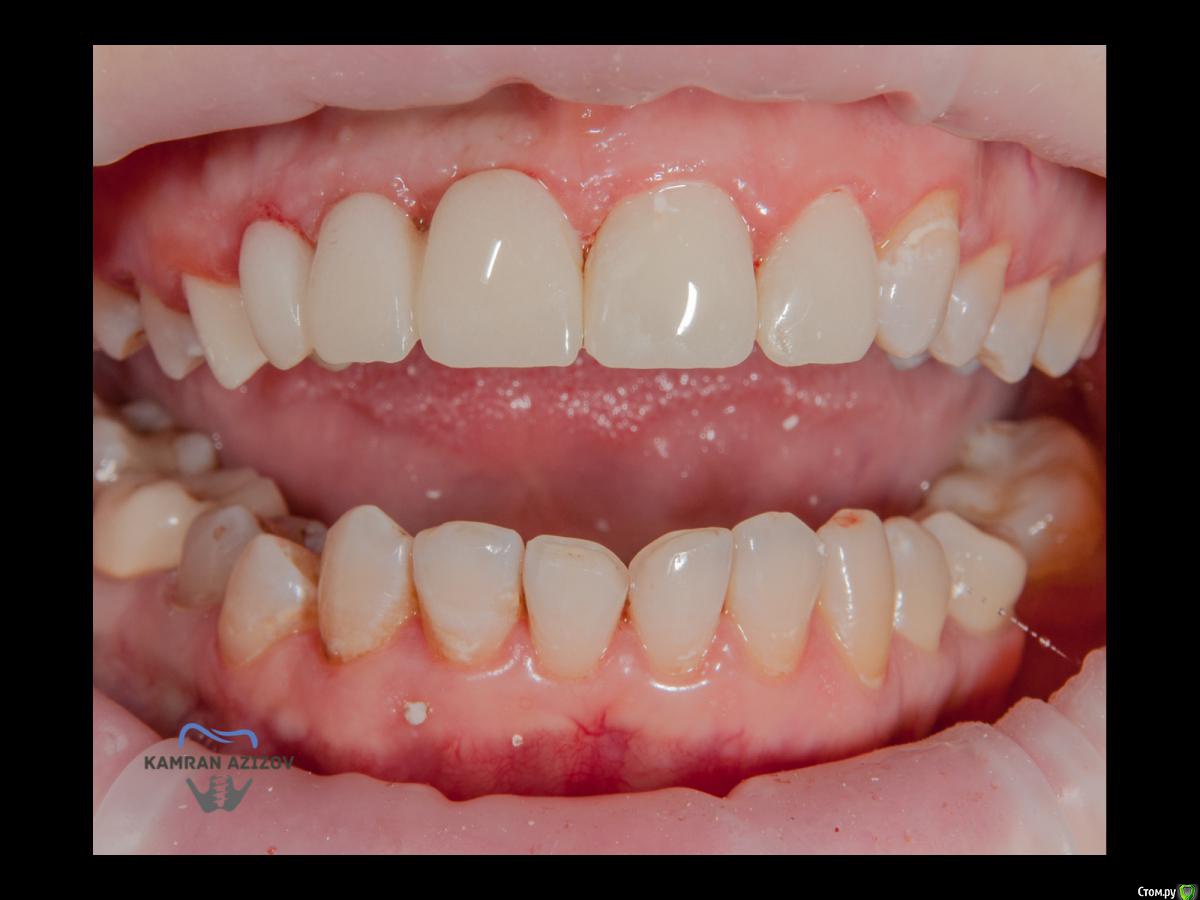

kamranchick Опубликовано 6 апреля, 2019 Поделиться Опубликовано 6 апреля, 2019 (изменено) Хай Гайсдавно ничего не комментировал и не выкладывал, что то настроения не было, да и муза не посещалаСитуация следующаяпришла пациентка, жалобы на неприятный запах из рта, сначала не понял что за хрень, ну как распилил мост понял че к чему... халтура.Ну и по кейсуУдаление клыка и 2ки, через 2 месяца навигация, имплантация + Шашлыки по карлоссу, смена формиков, временное протезирование. только мягкие ткани, Изменено 6 апреля, 2019 пользователем kamranchick 7 1 Ссылка на комментарий

kamranchick Опубликовано 11 апреля, 2019 Автор Поделиться Опубликовано 11 апреля, 2019 Рекол 6 месяцев Ссылка на комментарий